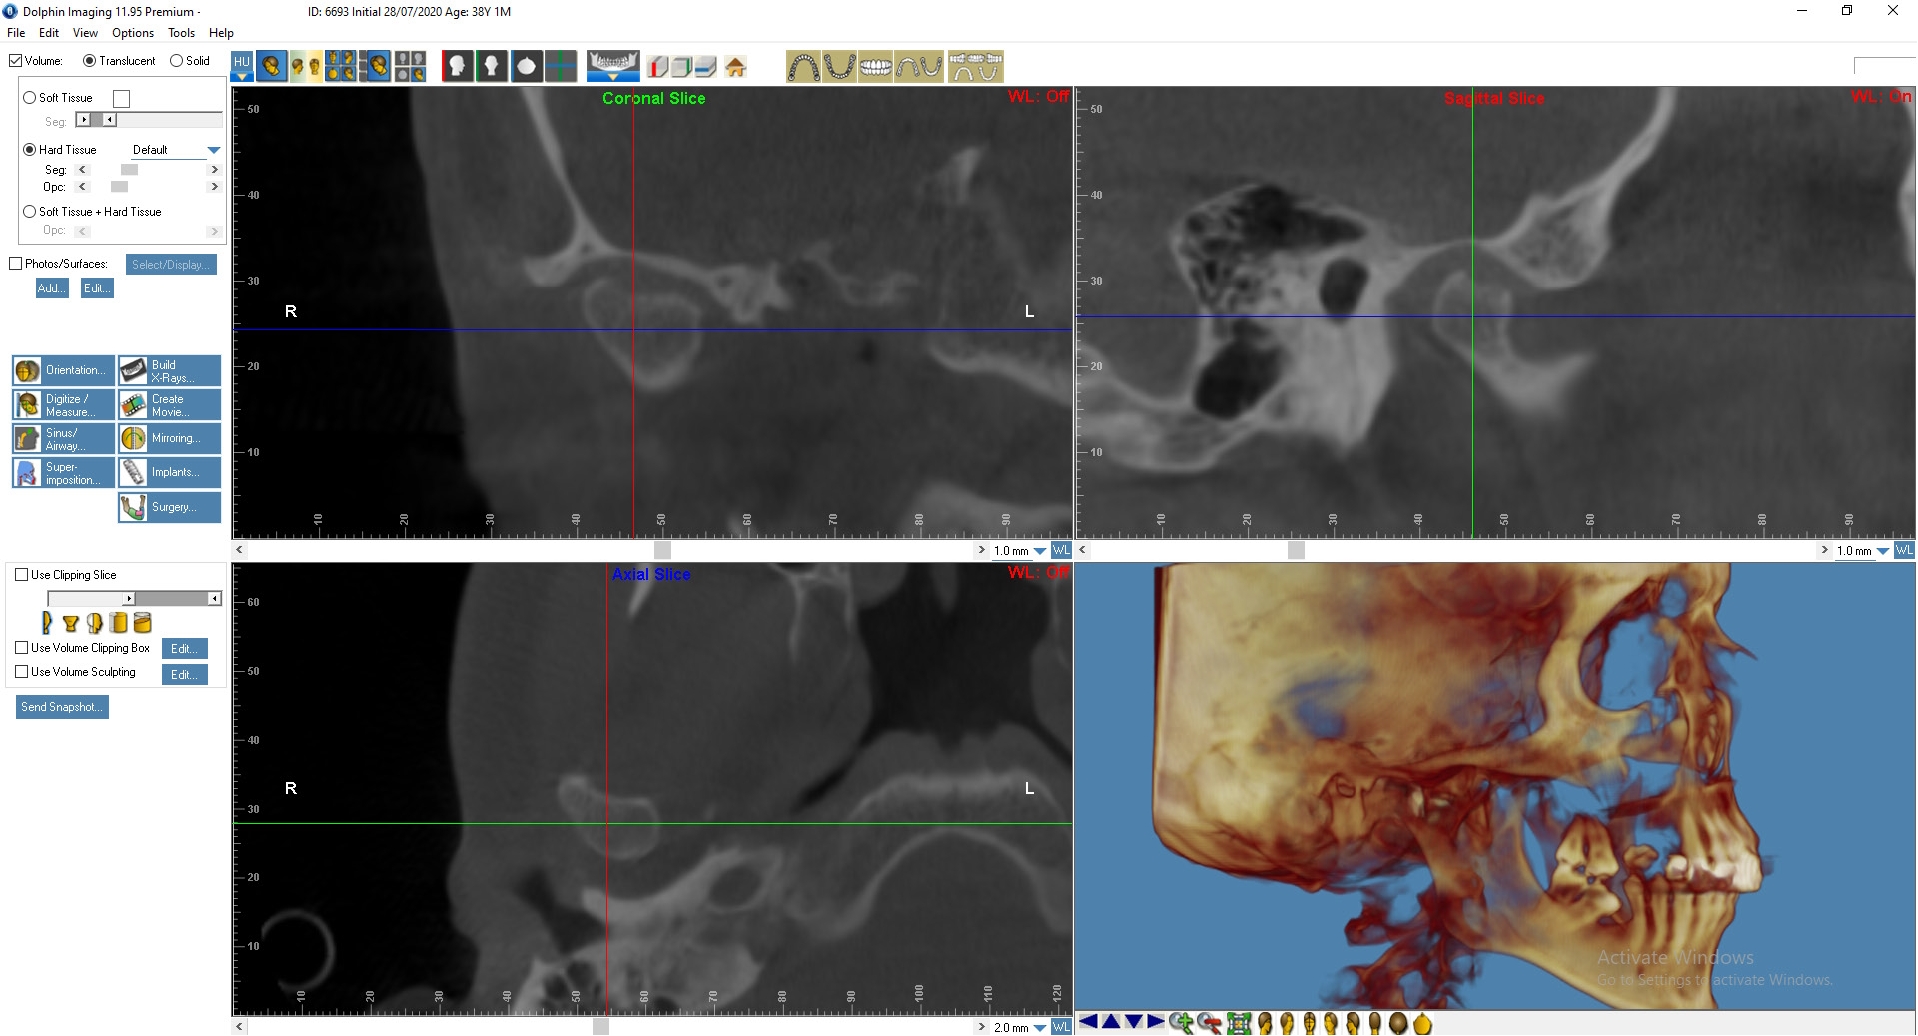

На основании КТ с использованием лицензионной программы Dolphin Imaging 11.95 Premium определяли цефалометрические параметры черепа и анатомические изменения в ВНЧС. Для интерпретации результатов МРТ использовали Radiant Dicom Viewer.

Пациенту была выполнена МРТ ВНЧС.

По данным МРТ: Артроз правого ВНЧ сустава 1-й степени. Полная вентро-латеральная дислокация суставного диска с репозицией. Гипомобильность сустава малой степени выраженности.

Артроз левого ВНЧ сустава 2-й степени, синовит. Полная вентро-латеральная дислокация суставного диска с частичной репозицией. Гипомобильность сустава малой степени выраженности. Начальные признаки фиброза биламинарной структуры.

Рис. 4. Пациент Д., 38 лет. КТ ВНЧС до начала лечения